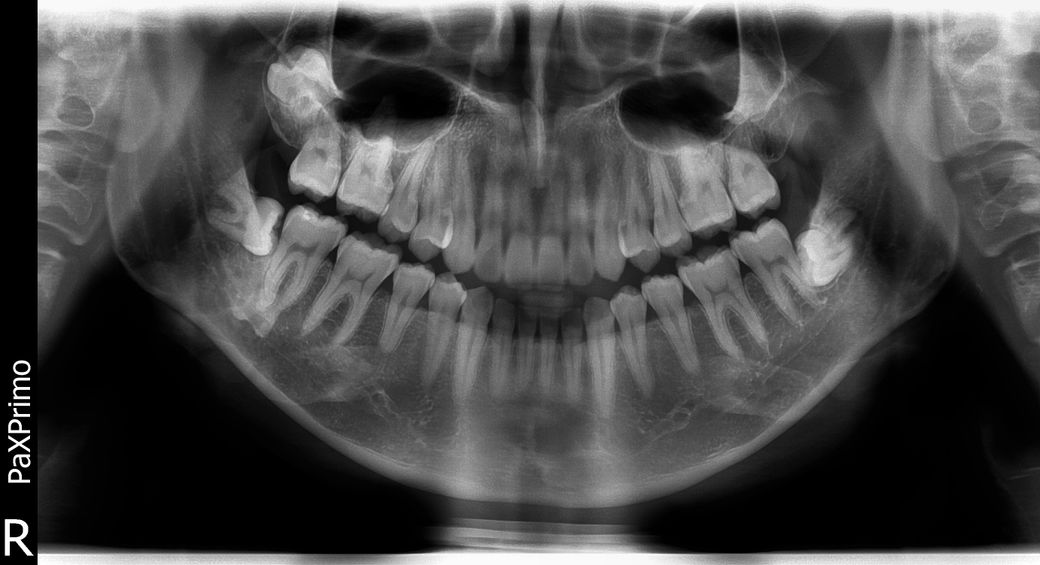

사진을 보시면 좌측(대칭으로 인해 사진 상 우측)이 비갑개와 자연공이 막혀있습니다

• 1번 째 사진